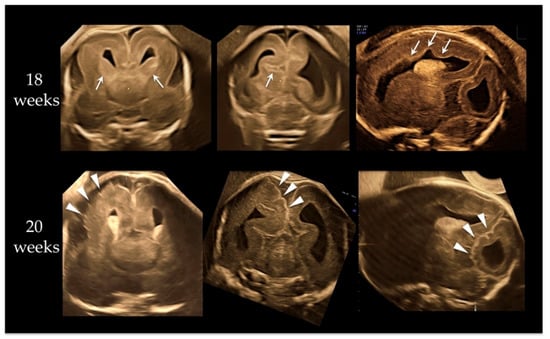

Fetal Megalencephaly with Cortical Dysplasia at 18 Gestational Weeks Related to Paternal UPD Mosaicism with PTEN Mutation